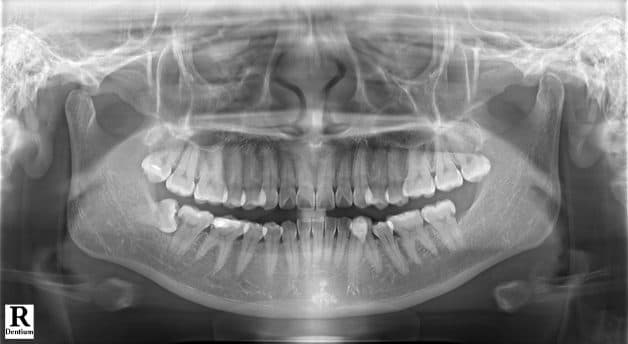

Qua thăm khám lâm sàng và chẩn đoán hình ảnh, bác sĩ Thu Cúc TCI xác định: Răng khôn hàm trên bên trái của anh mọc lệch, quanh nó có nhiều khe dắt thức ăn. Chính các khe dắt thức ăn này là nguyên nhân khiến nướu anh viêm tấy.